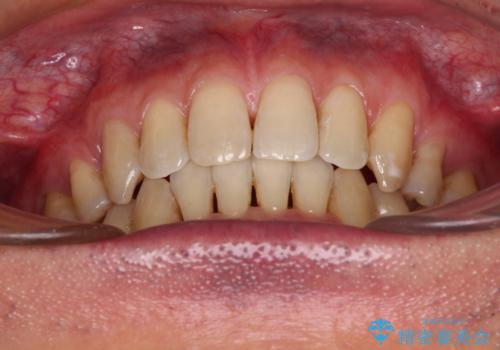

- 口元の閉じにくさと、前歯のでこぼこの歯並びを気にして来院された患者様です。

口元を積極的に引っ込めるために、上下左右の小臼歯計4本を抜歯することとしました。

叢生が強い場合、抜歯スペースが叢生を解消するために消費されるため、口元の突出感があまり改善されないことがあります。

今回の治療では、奥歯が前方に傾斜した歯並びだったため、奥に起き上がることで歯列が後方に移動し、横側からも口元が引っ込んだ感じが分かるほど改善されました。